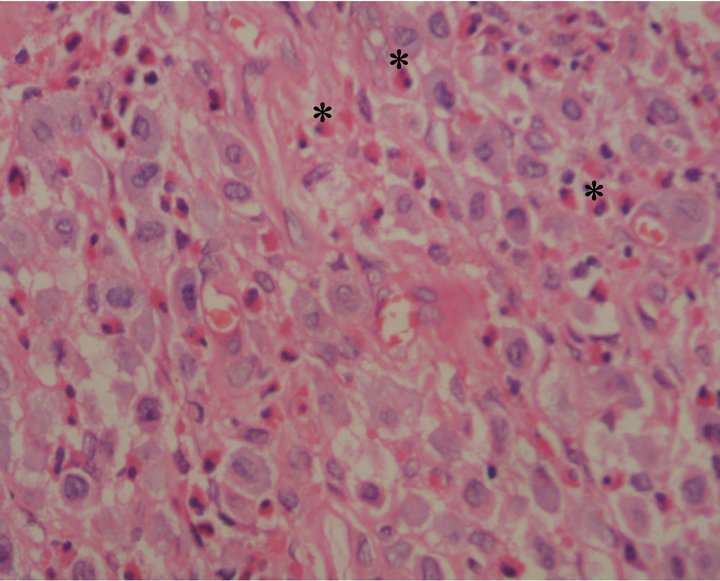

A 20 years old otherwise healthy female presented with a complaint of an asymptomatic lump for 3 years duration on the buccal mucosa to Oral Medicine clinic, Dental Hospital, Peradeniya, Sri Lanka. On examination it was a firm, painless nodule of 0.75 cm × 0.75 cm and the colour was similar to normal oral mucosa. It was smooth surfaced and well defined with intact overlying mucosa. None of the inflammatory signs were found in the lesion. Any history of trauma could not be elicited. As the nodule was small, excisional biopsy was performed without an incisional biopsy with the clinical diagnosis of either a reactive fibroepithelial lesion or enlarged facial lymph node. Histopathologically, the lesion was composed of solid sheets of mast cells containing abundant eosinophilic cytoplasm. There was a marked infiltrate of eosinophils in between the main cell population (Figure 1). These cells were confirmed as mast cells with the special stain Toluidine blue (Figure 2). All the hematological investigations which were carried out appeared to be within normal limits and there was no organomegaly and the patient is on regular follow up. There is no evidence of recurrence during the follow up period of more than 8 months.

Figure 1. Sheets of mast cells admixed with eosinophils (*) (H & E ×200).